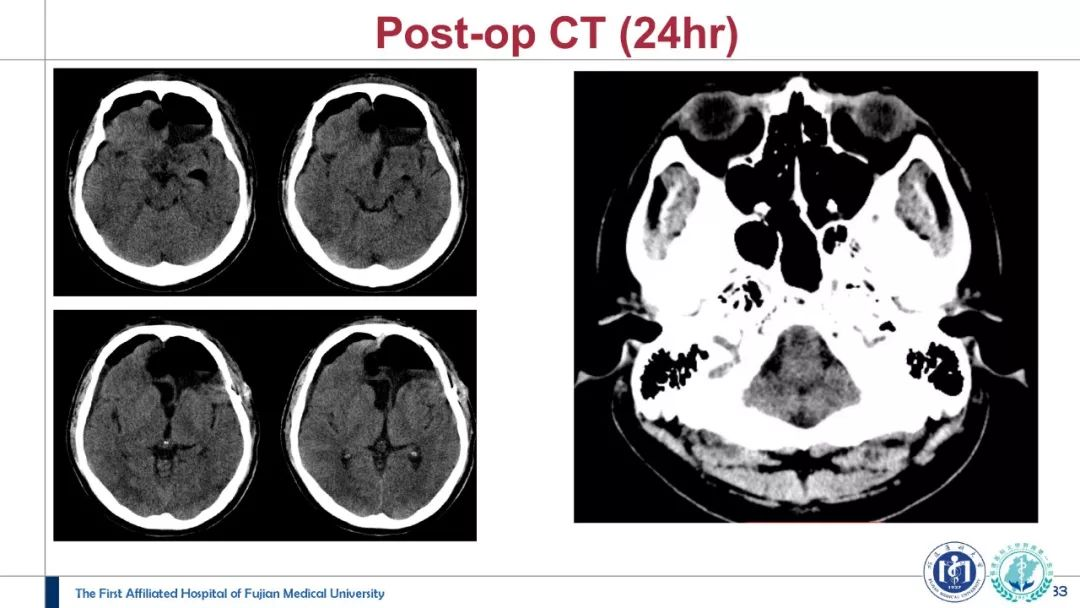

神外资讯将定期分享第一届“凝神聚胶”全国青年医师胶质瘤临床病例分析大赛的获奖病例。本期分享的病例是“二等奖”获得者——福建医科大学附属第一医院吴赞艺医师带来的:“Recurrent Anaplastic Oligodendroglioma Case Sharing(复发间变性少突胶质细胞瘤病例分享)”,欢迎观看、分享。